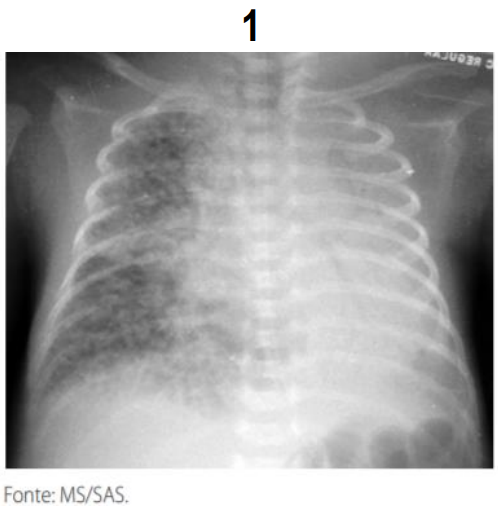

A radiografia de tórax é o exame de eleição para o diagnóstico das várias formas de SEAr. É fundamental, também, para a determinação do tamanho e da extensão da coleção de ar e da coexistência de outras entidades que possam facilitar ou perpetuar o escape de ar, além de permitir o acompanhamento evolutivo e avaliar a eficácia da terapêutica adotada. Na grande maioria dos casos o aspecto radiológico é típico, sendo possível definir o diagnóstico com relativa facilidade. Analise as imagens radiológicas com sinais patognomônico e assinale a alternativa da doença associada